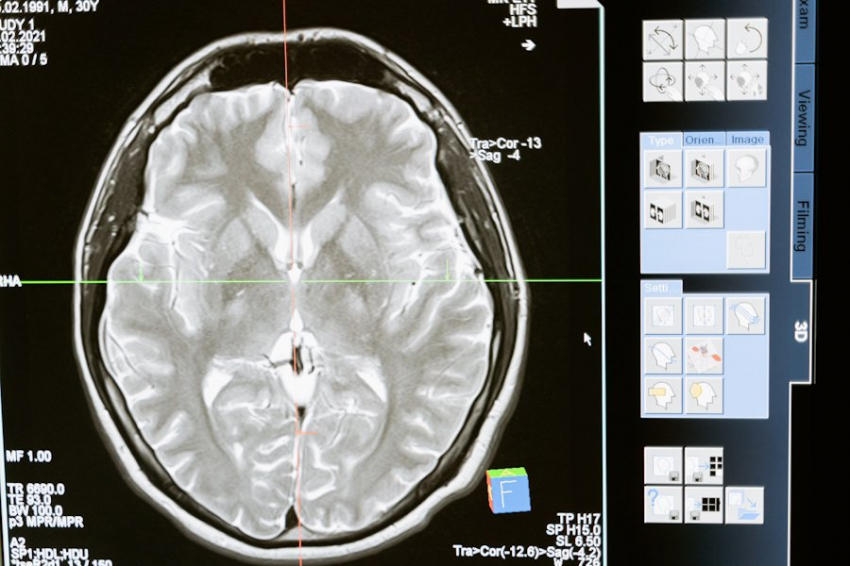

Фото из открытых источников Исследователи из Institute for Basic Science (IBS) (Республика Корея) провели успешные испытания новой методики Magnetogenetic Interface for NeuroDynamics (Nano-MIND), которая позволяет воздействовать на мозг человека без использования имплантатов. Эта технология объединяет магнитные...